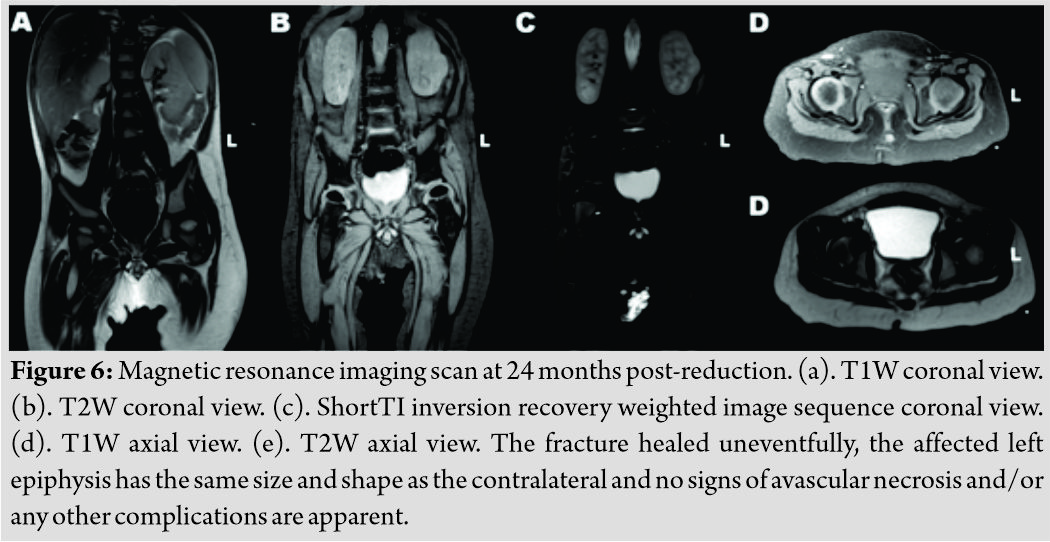

The patient was followed up at our outpatients’ clinic every week for the 1stmonth and then every 15 days for another month. The spicacast was removed at 8 weeks (Fig. 4). Physical examination at this stage revealed a painless hip with a full range of motion. The patient’s physiotherapy and passive kinesiotherapy routine resumed at 6-month post-reduction. Despite the fact that he was not able to walk (and remained non-ambulatory on his latest follow-up visit) suffering from severe psychomotor dysfunction in the context of epileptic encephalopathy, painless hip range of motion was retained during all follow-up visits throughout the next 22 months. Consecutive follow-up radiographs obtained during the follow-up period, revealed good remodeling of the proximal femur and a femoral head with spherical contour and with no signs of avascular necrosis or chondrolysis (Fig. 5). An MRI scan at 2 years post-reduction showed normal shape and size of the affected femoral head, with no signs of physeal arrest and/or avascular necrosis (Fig. 6). Nevertheless, the child is under a tight follow-up schedule and it will remain under close observation until he has reached skeletal maturity.

SCFE is a hip condition, usually affecting older children and adolescents during a period of rapid growth [9]. This rather infrequent condition is manifested even more rarely in children younger than 10yearsold. Slippage in this group of patients is often associated with obesity, endocrine or metabolic disorders, septic arthritis, radiation therapy, and trauma [1,3,10,11]. The standard treatment of choice for SCFE is operative. Surgical options include bone peg epiphysiodesis, in situ fixation (either with smooth Steinmann pins or a screw), closed reduction and pinning and less commonly hip dislocation with subsequent realignment and fixation of the epiphysis and open or arthroscopic osteochondroplasty, and proximal femoral osteotomy [12, 13, 14]. Hip spicacast was found to be the treatment with the worst results, with rates of avascular necrosis up to 9%, chondrolysis up to 20.5%, and osteoarthritis up to 53%. As a result, this treatment modality has largely been abandoned in the management of SCFE [14]. Prophylactic treatment of the contralateral hip is often advocated since bilateral idiopathic adolescent SCFE may occur in up to 25% of cases. Alternatively, the young patient is closely followed-up until epiphyseal maturation has been achieved, and immediate operative intervention takes place, should SCFE is manifested in the contralateral hip as well[12,14]. We report the first– to the best of our knowledge–case in the English literature, of non-traumatic SCFE occurring in a 10-month-old infant. Taking the patient’s age and medical history into consideration, as well as the fact that he was in a “pre-walking” stage of development, and following consultation with the pediatric neurologist who was responsible for his treatment, we decided to follow a non-operative treatment plan. These were also the reasons we decided to avoid any prophylactic intervention in the contralateral hip. SCFE was successfully reduced and the fracture healed uneventfully with the application of a simple spicacast. No signs of femoral head avascular necrosis and/or any other complications were noted 2 years post-reduction. The reader, however, should interpret these results with caution since SCFE in our case occurred in a very young infant and its pathogenetic mechanism was different from the one usually encountered in children of older age and adolescents. Although – with a few exceptions [15]– it is not currently indicated for the treatment of the vast majority of patients with SCFE, closed reduction and immobilization in a hip spicacast may be considered as an alternative treatment option in carefully selected patients.